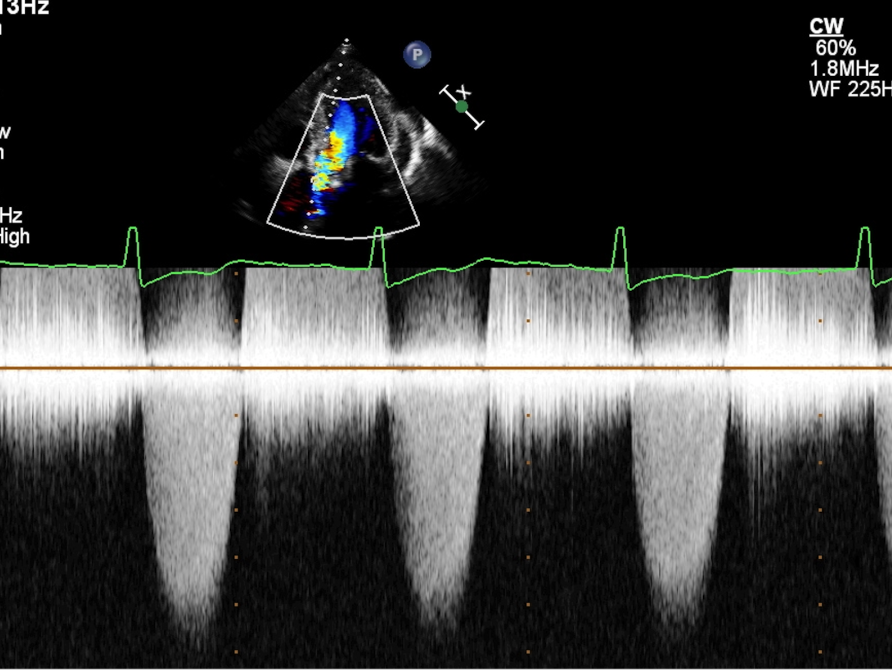

TTE